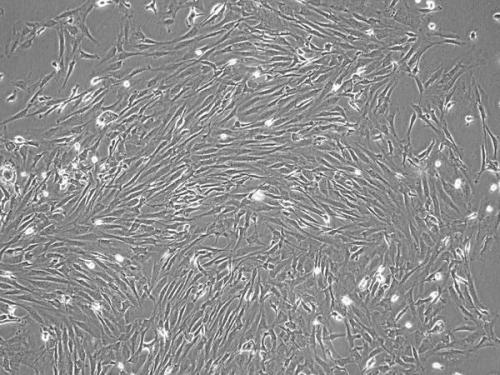

骨髓干細胞主要包括造血干細胞、間充質干細胞和內(nèi)皮祖細胞,是人體內(nèi)最原始的祖母細胞群。骨髓干細胞是骨髓中的主要支持細胞,具有造血、免疫調(diào)節(jié)以及較強的自我更新和多向分化潛能

骨髓干細胞主要包括造血干細胞、間充質干細胞和內(nèi)皮祖細胞,是人體內(nèi)最原始的祖母細胞群。骨髓干細胞是骨髓中的主要支持細胞,具有造血、免疫調(diào)節(jié)以及較強的自我更新和多向分化潛能,在骨髓移植后,受體內(nèi)的供體骨髓細胞不僅可以轉化為造血細胞,還可以分化為其他組織細胞,當機體處于生理或病理的狀態(tài)下,可動員骨髓干細胞釋放入周圍循環(huán)中而參與多種組織的再生。

近年來關于肝再生機制和骨髓干細胞(骨髓干細胞)的可塑性研究發(fā)現(xiàn),在肝硬化的動物模型實驗中,受體實驗小鼠在接受骨髓干細胞移植后,在肝組織內(nèi)特定的環(huán)境下可定向分化成肝細胞并參與結構和功能的修復和重建;體外誘導分化研究也證實,骨髓干細胞具有向肝細胞轉化的潛能。最近也有研究者在人體治療實驗中發(fā)現(xiàn)骨髓干細胞參與肝臟再生,能在肝臟中分化生長為具有功能的肝細胞,使肝硬化患者的肝功能得到效果明顯的恢復和重建。骨髓干細胞具有強大的可塑性和化學趨向性,可通過分泌骨髓基質,提供造血微循環(huán),在一定的微環(huán)境定向誘導下,可以分化為包括神經(jīng)細胞、心肌細胞、血管內(nèi)皮細胞、軟骨細胞以及肝實質細胞等多種細胞。首先報道大鼠骨髓中某個細胞群具有轉化為卵圓細胞,并進一步分化為肝細胞和膽管上皮細胞的潛能,這一發(fā)現(xiàn)為肝損傷再修復的研究提供了新思路。

采用性染色體雜交法,在移植男性骨髓或男性全肝的女性患者肝臟中,均發(fā)現(xiàn)有Y染色體陽性的肝細胞和膽管細胞,并在丙型肝炎合并膽汁淤積性肝纖維化的肝移植患者肝臟中,這種Y染色體陽性細胞表達比例更高。研究發(fā)現(xiàn)移植的骨髓干細胞不僅可以通過細胞融合和轉分化形成肝細胞,還可以通過旁分泌的方式刺激肝細胞再生。因此骨髓干細胞與肝細胞再生有著密切的聯(lián)系,受損肝臟是骨髓干細胞“著床”生存的微環(huán)境,也是向肝細胞定向誘導分化的最佳“土壤”。